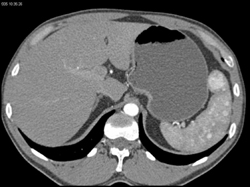

Splenic Hemangiomas